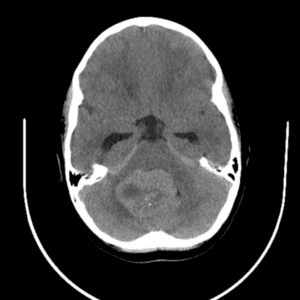

Case #14

CNS toxoplasmosis